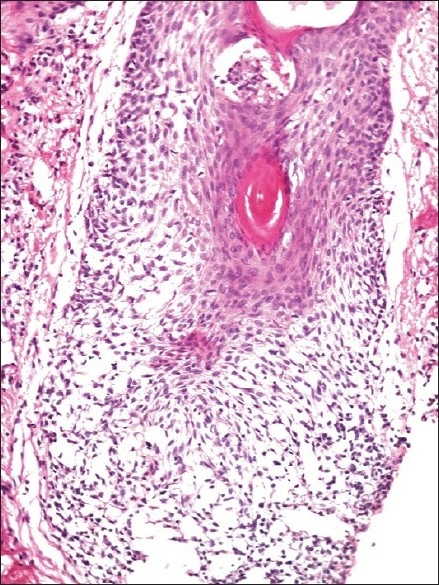

The histological features are depicted in Table 1. The most striking feature on biopsy, discernible even on scanning magnification, was a moderate-to-dense folliculotropic cellular infiltrate [Figure 2]. This infiltrate was populated by monomorphous lymphocytes in two cases, while the other two showed an admixture of many eosinophils (> 20 per section). There was invasion of the follicular units by these lymphocytes, with tagging along the basal layer in rows [Figure 3]. The infiltrate was seen involving the bulb of the follicle in all four cases, in addition to the isthmus in two cases. The lymphocytes showed enlargement and convoluted nuclei, surrounded by haloes. The case that showed a profusion of eosinophils also showed epithelioid granulomas centered on the involved follicles. [Figure 4] Special stains for fungi and Mycobacteria were negative. Mucin was present within the follicle in all four cases, which was highlighted by an Alcian blue stain [Figure 5].

| Figure 4 Ill-formed granuloma around the follicular units (H and E, × 200)